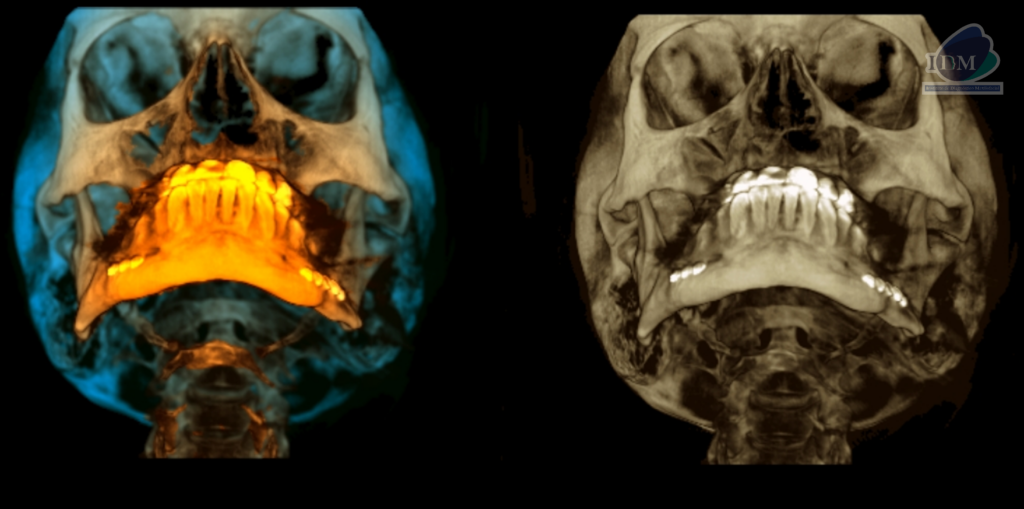

RECONSTRUCCIÓN 3D

Así mismo en la tomografía volumétrica de haz se confirma dicha mineralización, la cual se extiende desde base de cráneo hacia las astas menores del hueso hioides y presentado un patrón de mineralización pseudoarticulada.

- Mineralización bilateral de la cadena estilohioidea del tipo pseudoarticulada.